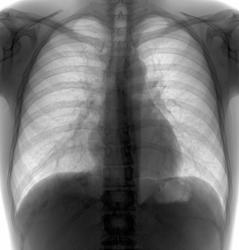

Случай 1.

Молодая барышня 28 лет. На момент проведения ц ФГ жалоб нет. Представлена для контроль аналоговая рентгенограмма двухнедельной давности. Динамика отсутствует (посему не выставляю)

В тот же день проведена КТ (о результате информирован лечащим врачом). Ваше мнение?